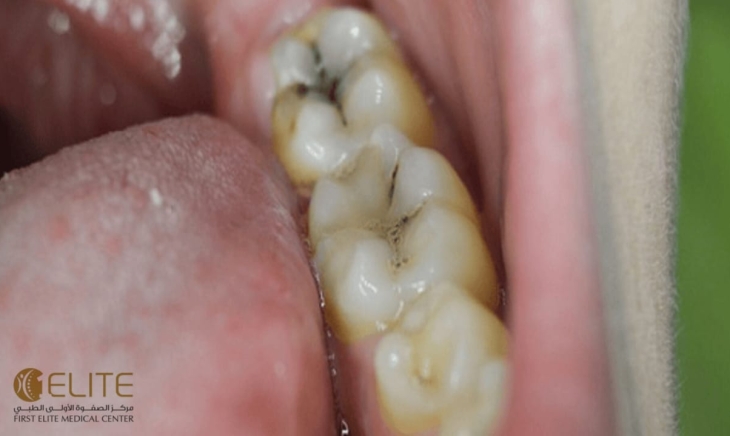

السكريات جزء لا يتجزأ من النظام الغذائي اليومي، لكنها تُعد من أبرز العوامل التي تُهدد صحة الأسنان. فالاستهلاك المفرط للسكريات، خاصةً في غياب العناية الفموية الجيدة، يؤدي إلى سلسلة من التفاعلات البيولوجية التي تُضعف الأسنان وتُعرضها للتسوس وأمراض اللثة.

عند تناول السكريات، تتفاعل مع البكتيريا الموجودة طبيعيًا في الفم، خاصةً تلك التي تُعرف باسم Streptococcus mutans. هذه البكتيريا تستخدم السكريات لإنتاج أحماض، وهذه الأحماض تبدأ في مهاجمة طبقة المينا (الطبقة الخارجية الصلبة للأسنان).

- إنتاج الأحماض التي تُهاجم المينا.

- تآكل المينا وظهور ثقوب صغيرة.

- تطور التسوس ليصل إلى طبقات أعمق من السن.